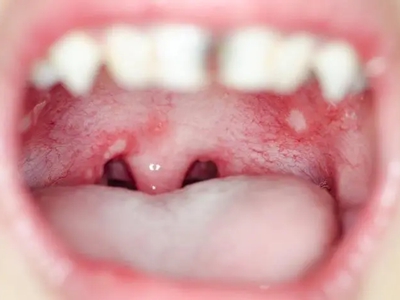

二期口腔梅毒会出现梅毒性黏膜炎及梅毒黏膜斑症状,梅毒性黏膜炎好发于舌、唇黏膜及口角等处,表现为黏膜充血、弥漫性潮红,可有糜烂。舌背有大小不一的光滑区,舌乳头消失。